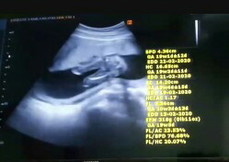

คุณหมอบอกว่าอาจได้ลูกสาว ดูตามคุณหมอยังไงก็ดูไม่ออก ดูวีดีโอก็แล้วดูรูปก็แล้ว อิแม่ได้ลูกสาวจริงๆใช่มั๊ย?? จะซื้อของละน๊าาา☺☺☺

แม่ลองสักเกตนะคะ ท่าเด็กนั่งเหยียดขาอะคะสมมุติเด็กนั่งอยุ่บนโต๊ะกระจกละคุณแม่อยู่ใต้โต๊ะละมองขึ้นมาที่ก้นลูกนะที่วงเล็กนั้นคืออวัยวะเพศ ถ้ามีแหลมๆออกมาหมอกะจะบอกว่า ผช แต่ถ้าไม่มีโอกาสเป็น ญ สูง

ผู้หญิงนะคะ ไม่เห็นจู๋โผล่

ผู้หญิงค่ะ ถ้าผู้ชายจะมีจู๋โผล่ออกมาค่ะ

ไม่มีไข่หราจู๋โผล่มาจ้า ได้หญิงชัวร์จ้า